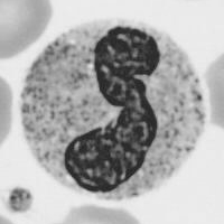

Medical Imaging (MI). Figure˜4d–f summarizes results on five datasets from the MedMNIST-v2 collection [yang_medmnist_2023]: PathMNIST, RetinaMNIST, BloodMNIST, DermaMNIST, and ChestMNIST. We use the standardized 224×224224\times 224 pixels version to ensure consistency with the experimental setup. Across these datasets, suppression effects are more heterogeneous than in CV. While shape suppression degrades performance, the impact is generally less pronounced, and texture suppression yields moderate performance drops in datasets such as PathMNIST and BloodMNIST, but relatively little effect in RetinaMNIST and DermaMNIST. By contrast, color suppression induces a substantial decline in classification accuracy for most datasets, reflecting the strong diagnostic role of chromatic cues, except in ChestMNIST, which contains only grayscale images. Taken together, these results suggest that feature reliance in MI varies substantially across datasets, with a common trend towards greater dependence on color information.

Visual examples of the applied feature suppression transformations are provided in Figure˜6 and Figure˜7, illustrating images from the entry-level categories dog and bird in the ImageNet validation set. Additional examples for the RS domain are shown in Figure˜16 and Figure˜17, corresponding to the classes farmland and beach from the AID dataset. For the MI domain, Figure˜18 and Figure˜19 present examples from the classes melanocytic nevi in DermaMNIST and neutrophil in BloodMNIST.